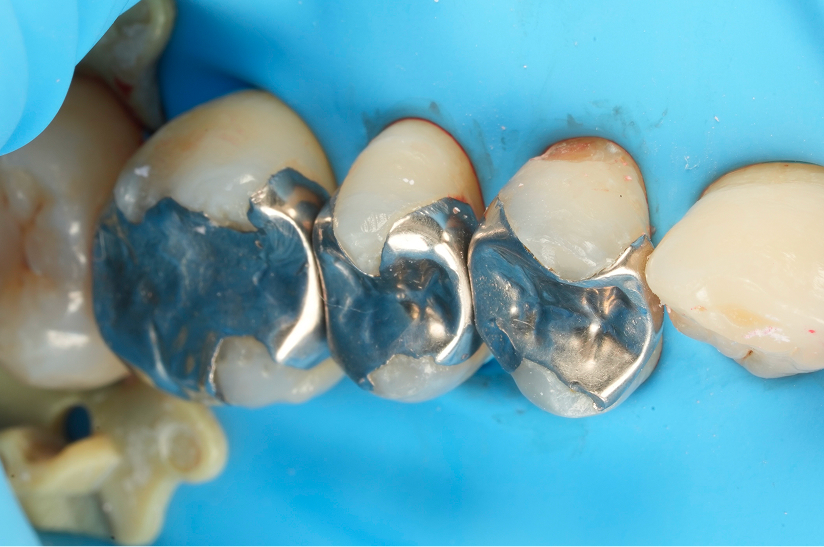

通常インレーになる二次カリエスの歯を

最小限の治療で修復した症例

Before

After

主訴

銀歯が外れたところを長持ちする方法で治療して欲しい

治療内容

ダイレクトレストレーション

治療費用

55,000

治療の

リスク

治療直後(24時間以内)に硬いものを噛むと知覚過敏症状が生じる可能性があります。